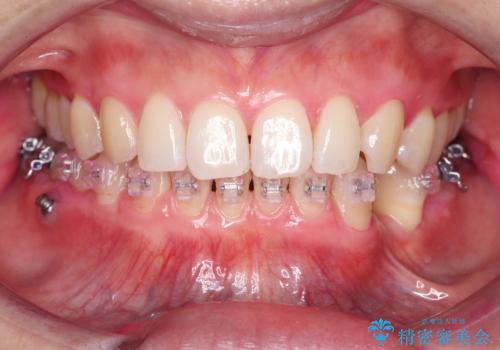

- ワイヤー矯正中の患者様です。

今回は汚れを染め出しクリーニングをしました。

ワイヤーの装置周りは歯ブラシが当てにくいので、歯石や歯垢などが残り歯周病・虫歯になりやすいです。そのため定期的なクリーニングをおすすめしております。